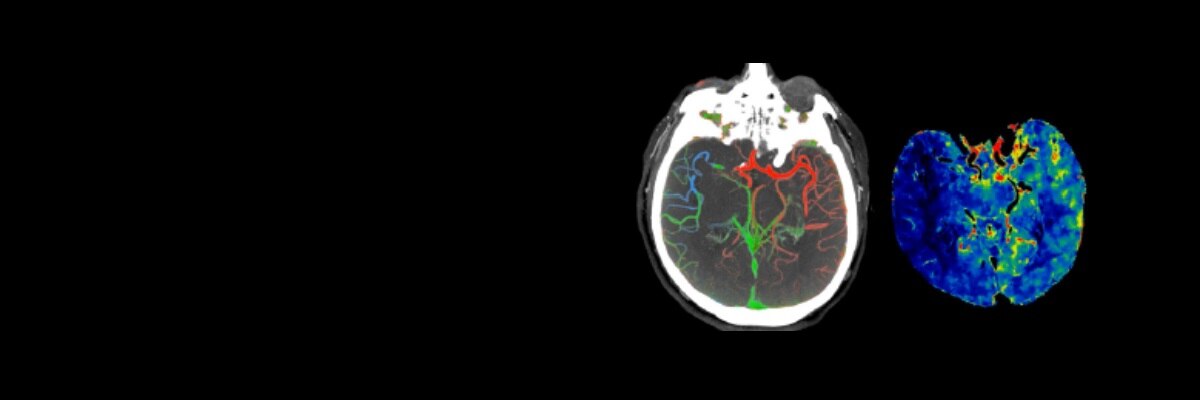

Imaging